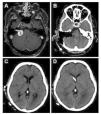

El síndrome pierde sal cerebral (CSW, en sus siglas en inglés) es una complicación rara en la cirugía de los tumores de la fosa posterior. Presentamos a 2 pacientes con tumores del ángulo pontocerebeloso que desarrollaron un CSW posquirúrgico. Ambos pacientes tuvieron un empeoramiento pese a la fluidoterapia y la reposición de sal intensivas. La tomografía computarizada (TC) mostraba una dilatación ventricular leve a moderada que fue tratada mediante un drenaje ventricular externo. Tras la resolución de la hidrocefalia el balance hidroelectrolítico se normalizó rápidamente en ambos pacientes y su situación clínica mejoró. La identificación y el tratamiento precoz de la hidrocefalia obstructiva pueden contribuir al tratamiento del síndrome pierde sal asociado a la cirugía de tumores de la fosa posterior.

Cerebral salt wasting (CSW) is a rare complication in posterior fossa tumour surgery. We present two patients with cerebellopontine angle (CPA) tumours who developed cerebral salt wasting postoperatively. Both patients deteriorated in spite of intensive fluid and salt replacement. On CT scan the patients presented mild to moderate ventricular dilation, which was treated with an external ventricular drainage. After the resolution of hydrocephalus, fluid balance rapidly returned to normal in both patients and the clinical status improved. Identification and treatment of secondary obstructive hydrocephalus may contribute to the management of CSW associated to posterior fossa tumour surgery.